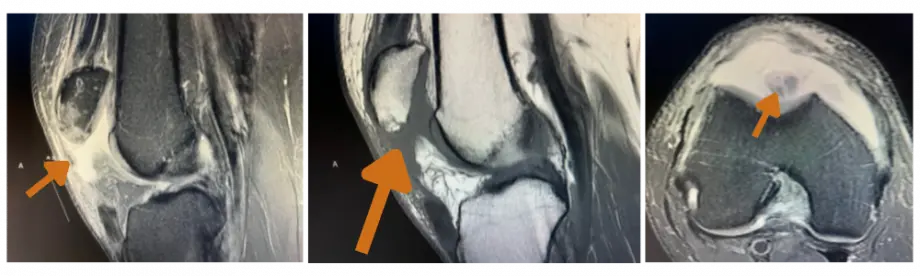

John: Background: I partially tore my patellar tendon playing basketball a couple of months before I fully ruptured it stepping into an unseen hole coming off a tee box, on the golf course, in April. Coming off the tee box, my knee immediately buckled, and my patella dislocated. I was fortunate to be able to self-reduce this at the time of the injury, then used an immobilizer. MRI results showed a completely torn patellar tendon from the inferior aspect of the patella. This required surgery to repair which was completed by Dr. Kevin Stanley.